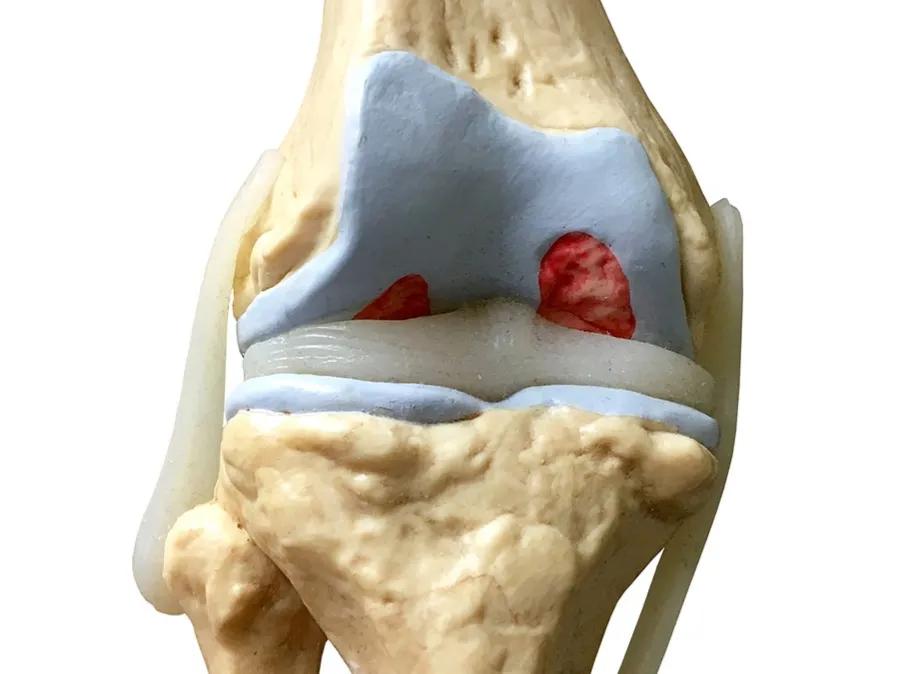

氨基葡萄糖是一种在体内自然产生的氨基糖,它是合成 糖胺聚糖 (GAG) 的基础材料,例如 硫酸软骨素 和 透明质酸 ,这些 糖胺聚糖 是关节软骨中 蛋白多糖 的关键成分。

那蛋白多糖是啥呢?它是关节软骨的重要组成部分,它分子巨大,有较大的粘滞性,附着于组织表面,能 缓冲组织之间的机械磨擦,因而具有润滑、保护作用。

我们可以把关节软骨想象成一片大草原,地面上的草丛就是构成关节软骨的 胶原纤维 ,而起到维护草原整个秩序的是在草原中分布广泛的雄狮!那这些 雄狮就是蛋白多糖 ,在关节内起到了极其重要的 抗压、增强软骨强度以及润滑 的作用!

雄狮(蛋白多糖) 的成分很复杂, 氨基葡萄糖 是合成它的重要成分之一!

骨关节炎,也叫 退变性关节炎 或 老年性关节炎 ,其主要的病理基础就是 关节内软骨的磨损 ,随着年龄的增长、长期的使用以及外伤等因素,关节软骨表面不再光滑,磨损日渐加重,患者就会出现关节的疼痛、酸胀以及功能受限,严重的会导致残疾,它是老年人致残的主要原因之一。

但有一点要注意,那就是 骨关节炎患者的病情不能太重,适合早期和中期患者服用 ,如果经过检查患者的关节软骨磨损极其严重,关节间隙出现了明显的狭窄,关节周边已经有大量的骨赘形成,到了骨关节炎晚期的程度,就没有必要尝试了, 雄狮已经消失了,再补充养分也于事无补了 ,就是这个道理。